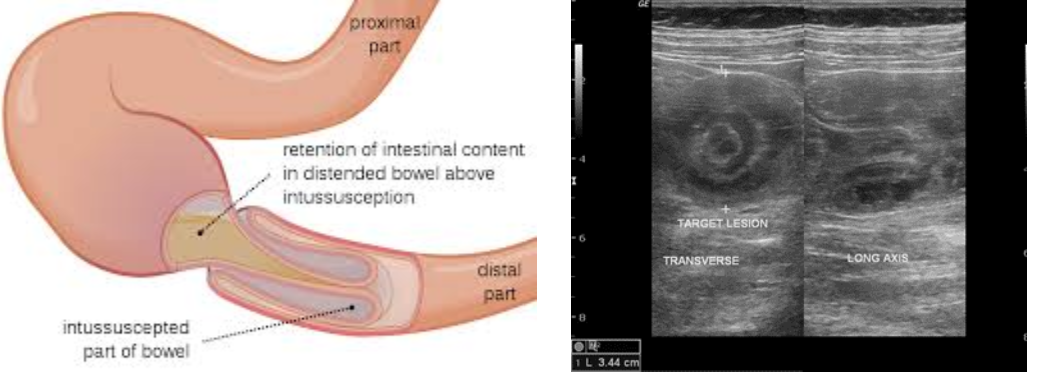

Intussusception in Children: What Parents Should Know